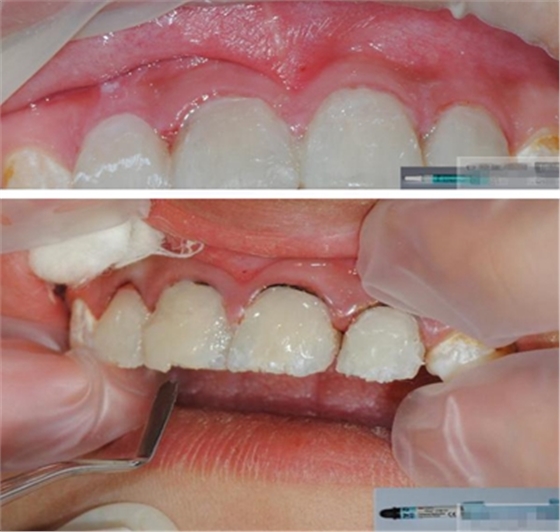

【主訴】上前牙充填物脫落兩個(gè)月

【病史】上前牙一年前行根管治療,充填物部分脫落,自覺(jué)影響美觀,從不敢笑,要求先行樹(shù)脂修復(fù)。(年齡:14歲)

【檢查】12,11,21,22,均行玻璃離子充填,各牙不同程度部分充填物脫落,探(—),叩(—),冷刺激無(wú)反應(yīng),無(wú)松動(dòng),牙齦顏色粉紅,質(zhì)地堅(jiān)實(shí)而有彈性,點(diǎn)彩正常,牙結(jié)石(—);牙髓活力測(cè)試無(wú)反應(yīng)。

【診斷】12,11,21,22牙體缺損

【口內(nèi)簡(jiǎn)單充填】臨時(shí)充填 可以玻璃離子 也可以樹(shù)脂(不涂布酸蝕、粘結(jié)劑)

樹(shù)脂修復(fù)【診斷蠟型制作】美學(xué)蠟型可以使患者對(duì)可以達(dá)到的修復(fù)效果有直觀的了解,而且,患者也可以依據(jù)自己的美學(xué)素養(yǎng)對(duì)修復(fù)效果提出修改的意見(jiàn);